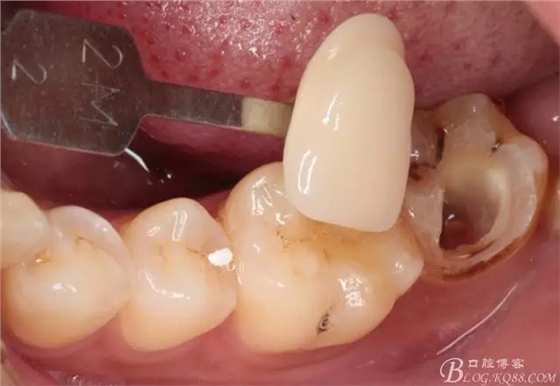

第四次復診,37叩(—)。此次行冠部修復,因涉及38的拔除,患者不愿拔除,與患者介紹修復材料與方法,擬37E.max嵌體修復,術前常規(guī)簽修復知情同意書。

去除暫封物,拍照,比色。

流動樹脂充填窩洞,金霸王車針和鎢鋼車針常規(guī)備牙,配合硅膠尖拋光,頰側排00排齦線。硅橡膠二次法取模,記錄咬頜關系,臨時樹脂充填窩洞。